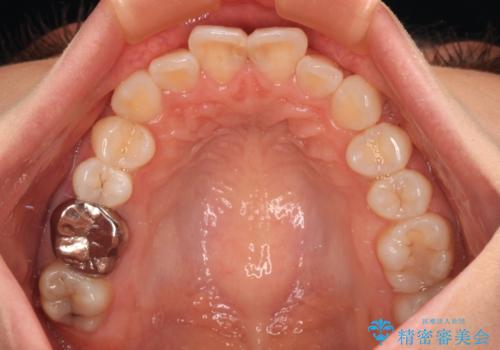

- 上下前歯のデコボコを改善したいとのことで来院された患者様です。

初めの1年くらいは何とか頑張って装着してくださいましたが、途中から変化をあまり感じられなくなり、日々の装着時間は徐々に短くなってしまいました。

前歯のデコボコはもっと改善できましたが、3年半が経過し、初診時と比べたら大幅に良くなったとのことで終了することとなりました。